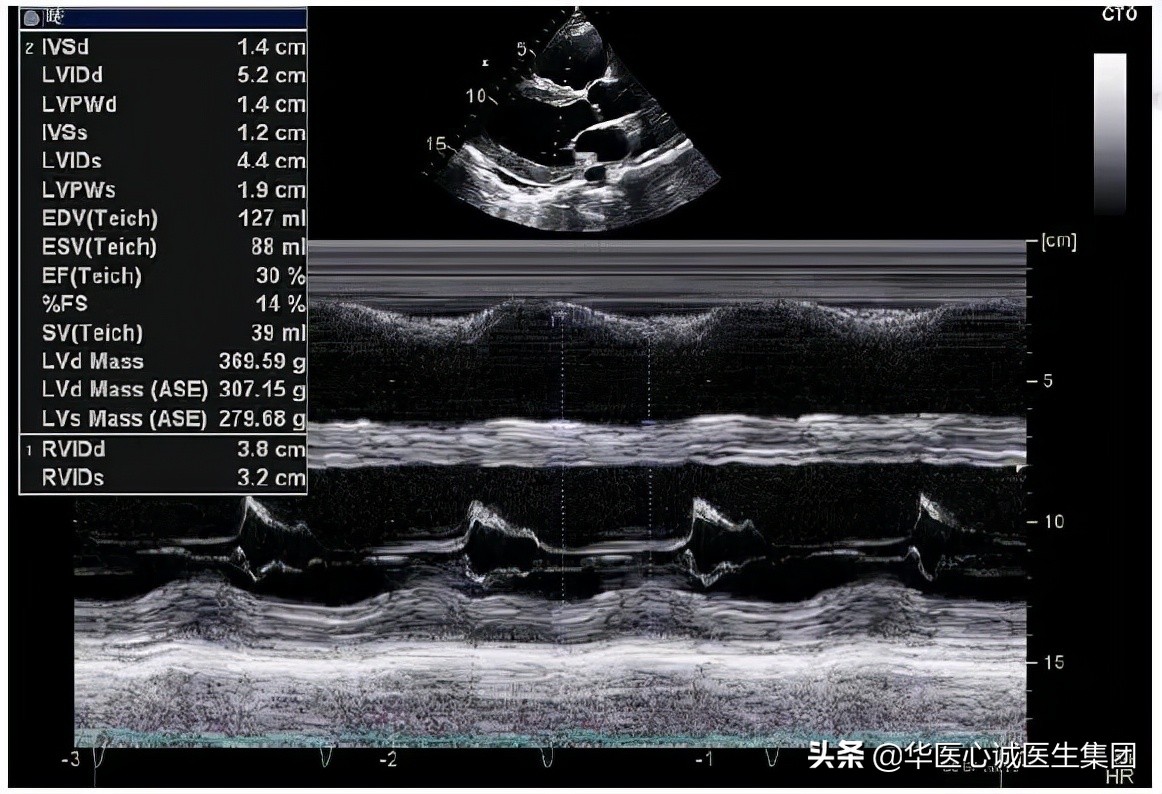

室壁1.4cm。

左室质量达到370克,LVMI>95g/m2,符合左室肥厚的标准。

EF值降低,为30%。